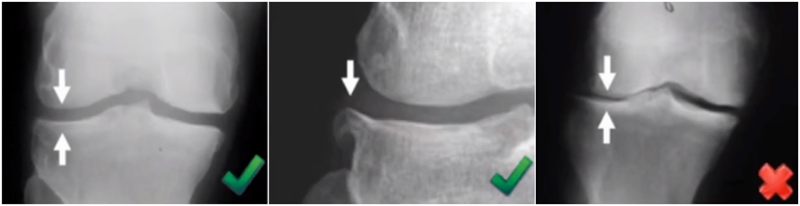

检查时注意X线的投照角度要平行于关节线方向,以保证准确。

标准侧位片,内外髁完全重叠,胫骨平台也一样,如果检查不标准,X线片结果会影响判断。

小结:判断股骨胫骨假体位置,是基于局部X线的判断,是考虑行走时关节线的方向为基准,此时内外翻不能超过5°,而不能从全长片来判断。